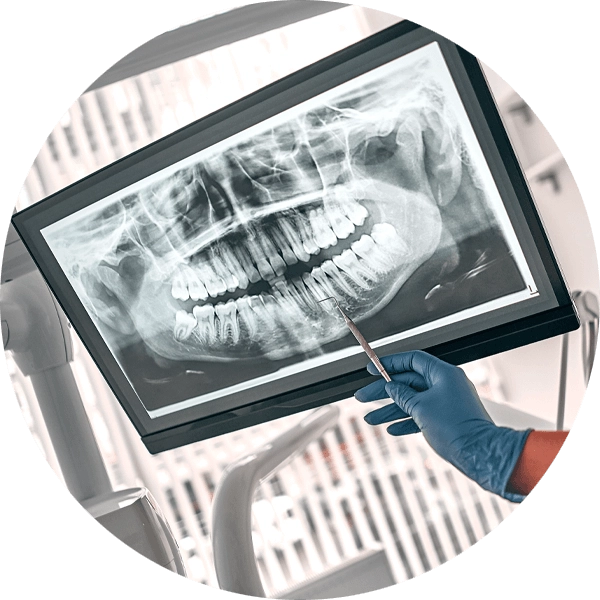

The decision to perform an extraction is typically straightforward when a tooth is impacted by significant decay, severe periodontal disease or a fracture. In addition, impacted wisdom teeth nearly always need to be extracted. Digital X-rays are used to analyze the underlying structures and determine if the tooth can be saved. If there is a pulp infection without a tooth fracture, root canal therapy is a highly successful method for preventing extraction. Extraction of normal teeth may be required for orthodontics, full mouth dental implants or when a primary tooth hasn’t fallen out and is stopping a permanent tooth from erupting. At Kari Mann Dental Studio in Cape Coral, our goal is always to save natural teeth, however, if conservative treatment is ineffective, extraction may be necessary. Extraction of a damaged or abscessed tooth can prevent more serious issues from impacting other teeth, your oral health and even your physical health. Regardless of the reason, Dr. Kari Mann has extensive expertise performing gentle tooth extraction in Cape Coral, FL. With a local anesthetic and sedation if you need it, tooth extraction will alleviate acute or chronic tooth pain and restore your oral health.